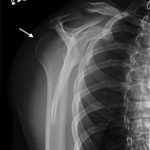

Radiographs demonstrated posterior displacement of the humeral head on the “Y” view (see white arrow) and widening of the glenohumeral joint space on anterior-posterior view (see red arrow). The findings were consistent with posterior dislocation and a Hill-Sachs type deformity. Sedation was performed and reduction was attempted using external rotation, traction counter-traction. An immediate “pop” was felt during the procedure. Post-procedure radiographs revealed a persistent posterior subluxation with interlocking at posterior glenoid. CT revealed posterior dislocation with acute depressed impaction deformity medial to the biceps groove with the humeral head perched on the posterior glenoid, interlocked at reverse Hill-Sachs deformity (see blue arrow).